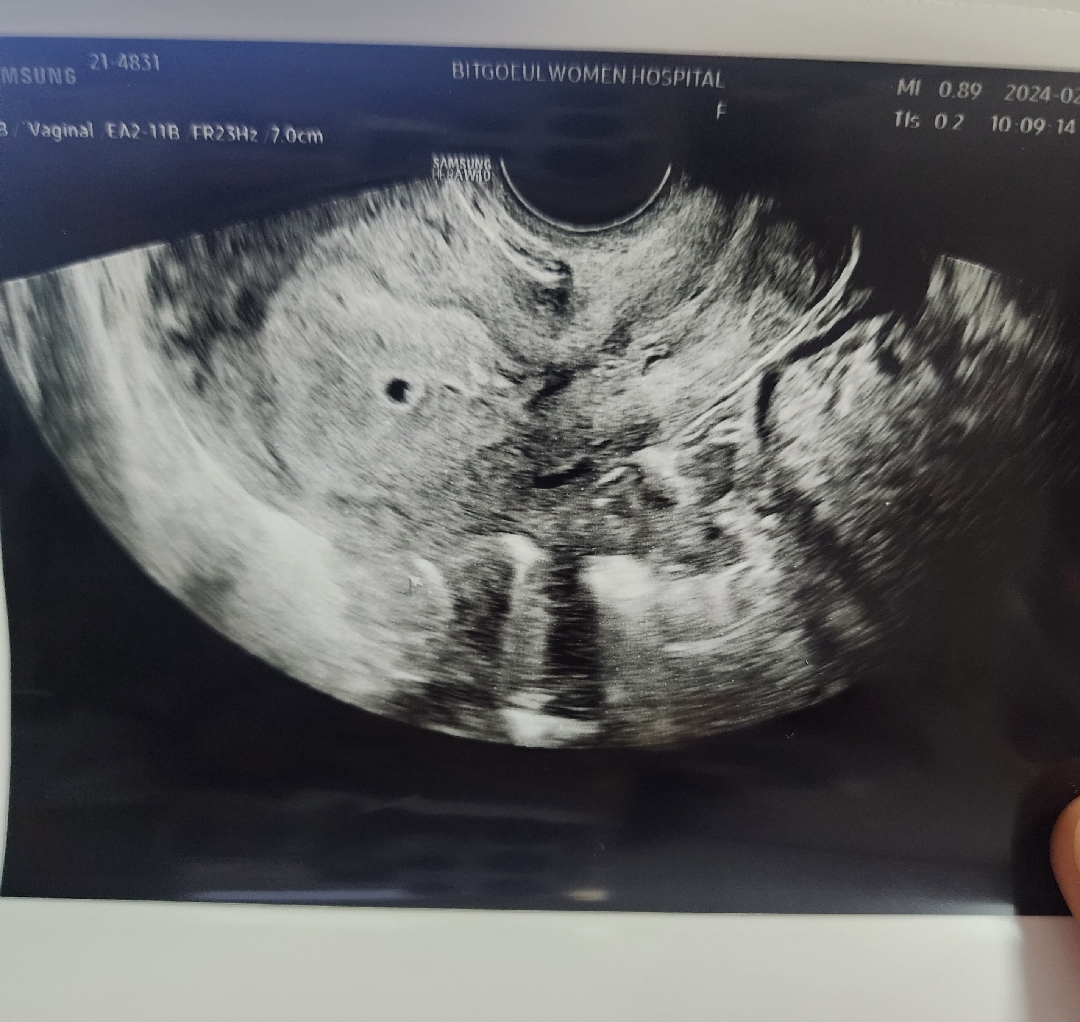

내일 초음파 검진인데 지난 주 초음파 보다가 하트처럼 보여서 올려봐요 쪼끄만게 자라날 생각을 하니 너무 신기해요